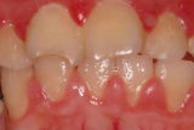

軽度歯周炎(歯肉炎)

歯周ポケット(歯と歯ぐきの間の溝)が3mm以内で、歯槽骨の破壊が起こっていない場合は、ほとんどが完治します。

歯肉炎では、プラーク(歯垢:生きた細菌の塊)や少量の歯石(プラークが石のように硬くなり、歯にこびりついたもの)がたまり、歯ぐきに炎症が起こり、赤く腫れたり出血したりといった症状が出ます。

軽度歯周病の症例です。歯ぐきが赤く腫れて炎症を起こしています。

細菌の侵入は歯肉で止まっています。

歯を支えている顎の骨はまだとかされていません。